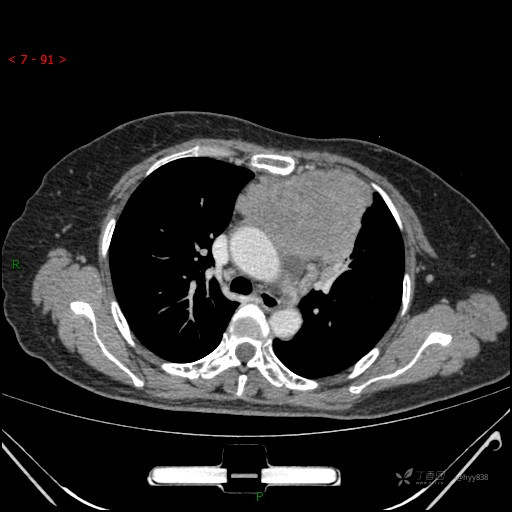

辅助检查:CT

胸部CT平扫

动脉期